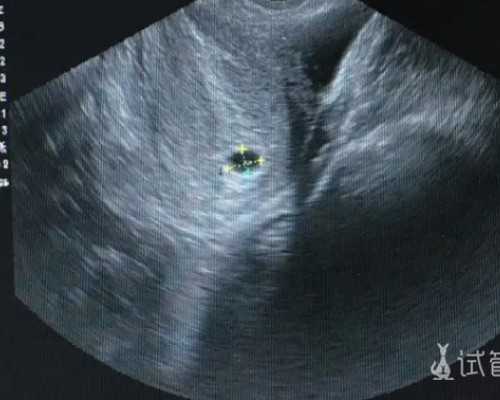

在B超声的监测下,“空卵泡”似乎发育正常,但当取卵时,卵泡无法取卵,卵泡是空的。空卵泡会导致卵子数量减少,从而影响率。之所以会出现这种情况,是因为每个卵泡的发育进度大多不一致,卵子脱离卵泡的时间也会有所不同,所以出现了空卵泡。但是你不用太担......